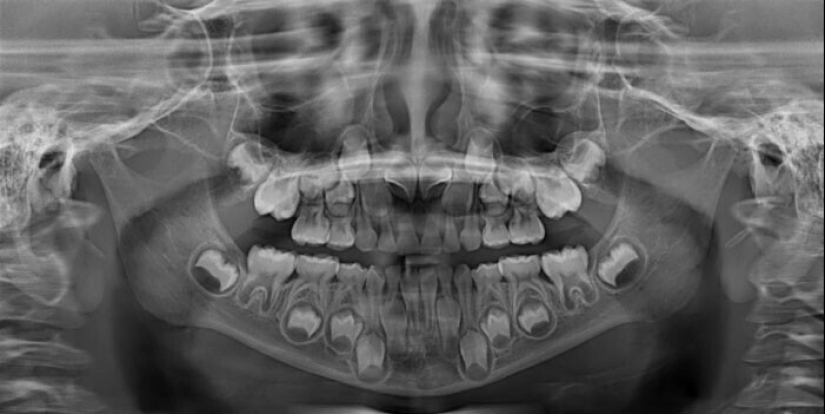

"Soy un dentista, pero los rayos x de los niños de 6-12 años me asustan un poco todavía"